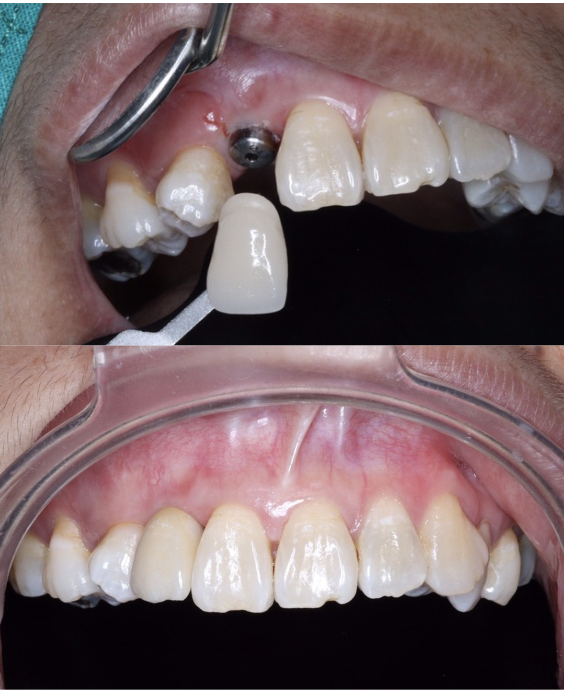

ฟันโยกทั้งปาก ฟันเสียหลายซี่มาก ต้องทำรากเทียม

ทั้งหมดเกือบ 10 ซี่ หลังทำเสร็จหนุ่มขึ้นมาก อยากกิน

อะไรก็กินได้ ตอนทำเจ็บนิดเดียว — คุณทนงศักดิ์